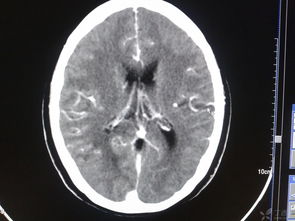

頭部損傷后常會發(fā)生繼發(fā)性顱內(nèi)損傷,其中最為嚴(yán)重的是顱內(nèi)血管破裂,形成顱內(nèi)血腫。

顱內(nèi)血腫形成后會使顱內(nèi)壓增高,使腦組織發(fā)生缺血、缺氧、水腫,顱內(nèi)壓力逐步增高,迫使部分腦組織發(fā)生移位而被擠進(jìn)顱內(nèi)生理孔道,形成危及生命的腦疝。 頭部受傷在天災(zāi)與人禍、戰(zhàn)爭與和平、生活與勞動中均十分常見,其病情危急,變化無常,后果嚴(yán)重。

顱內(nèi)血腫形成后會使顱內(nèi)壓增高,使腦組織發(fā)生缺血、缺氧、水腫,顱內(nèi)壓力逐步增高,迫使部分腦組織發(fā)生移位而被擠進(jìn)顱內(nèi)生理孔道,形成危及生命的腦疝。由于傷者家屬甚至一般醫(yī)護(hù)工作者對顱內(nèi)血腫和腦疝的發(fā)生規(guī)律、臨床表現(xiàn)和危害性缺乏深刻了解,或因傷后過早進(jìn)行腦CT掃描(其時出血尚未發(fā)生,血腫尚未形成),對傷員觀察欠仔細(xì),延誤診斷和治療,結(jié)果發(fā)生傷員不幸死亡的悲劇。

第二天上午10時,其妻見他口吐白沫,呼之不醒,急送醫(yī)院,腦CT掃描發(fā)現(xiàn)巨大硬膜下血腫,11時這位民工呼吸心跳停止。 3、肢體癱瘓:受傷時肢體運(yùn)動正常,逐漸出現(xiàn)步態(tài)不穩(wěn),走路搖搖晃晃,一側(cè)上肢或下肢乏力,抬舉困難。

4小時后其父親又將其送回急診室,主訴是眩暈難耐,惡心不適,站立不穩(wěn),分不清日期。CT掃描證實(shí)為硬腦膜外血腫,開顱手術(shù),未遺后疾。

此為家人警惕性高、觀察到病情變化及時復(fù)診、醫(yī)生及時診斷并手術(shù)成功的典型病例。 目前診斷顱內(nèi)血腫最可靠最快捷的手段是CT掃描,它能在數(shù)分鐘內(nèi)清晰地顯示出血部位、血腫大小和伴隨的其他情況。

顱內(nèi)血腫若能及時診斷和手術(shù),病人是可以完全康復(fù)的。